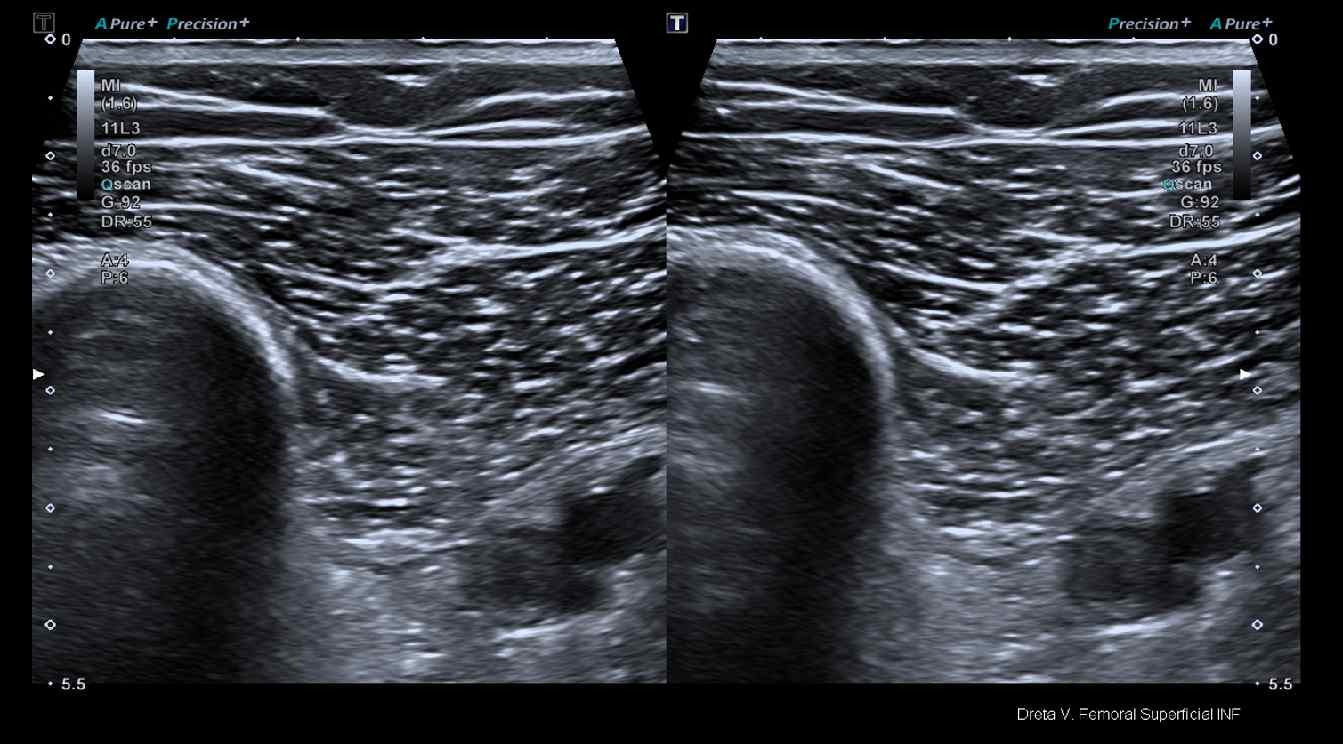

Hallazgos ecográficos

ECO TVP: impresiona de ocupación prácticamente total de la luz, ausencia de compresibilidad, con flujo sanguíneo por doppler en aproximadamente un 20%, de la vena femoral en zona proximal. La ocupación de la luz persiste en unos 4 cm de longitud. En vena poplítea si se observa flujo sanguíneo correcto.